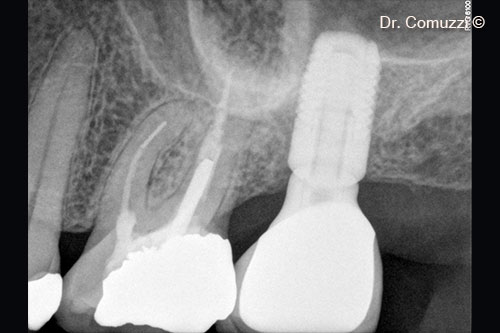

4. Implant insertion (Astra, 9-mm length and 5-mm diameter)

6. X-ray of Sinus Lift at implant placement